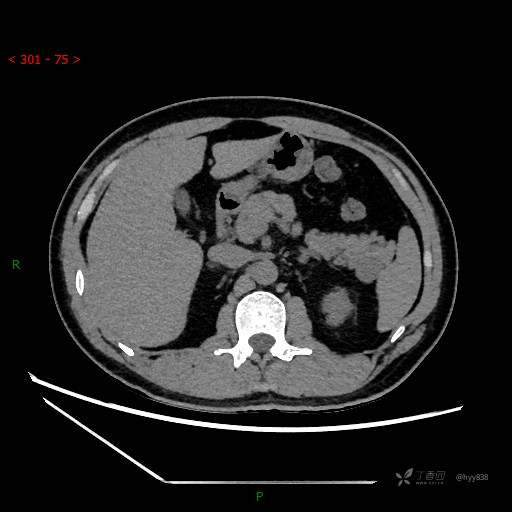

胰腺CT平扫

增强动脉期

增强静脉期

CT值

42hu 48hu 57hu